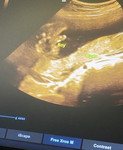

10weeks preggy

Normal ba na hnd pa mkkafeel ng pitik mga moms? Napapraning ako kasi last check up ko healthy si baby ,tas ngayon nagwowory ako kasi hnd ko mafeel kahit pitik man lang ni baby ๐ฅบ

its ok. maliit pa si baby kaya hindi pa maramdaman most ang fetal movements. mas ramdam at 6months.